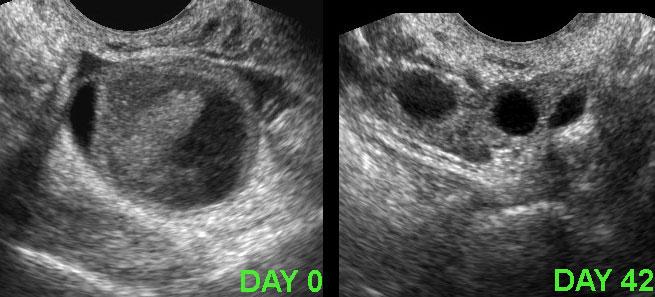

Ca lâm sàng 1

Ở người phụ nữ trẻ này, phát hiện một khối lớn dạng nang một phần với thành phần đặc, không có mạch máu (cục máu đông).

CRP duy trì ở mức thấp và cơn đau biến mất sau hai ngày.

Siêu âm theo dõi sau 6 tuần cho thấy hình ảnh hoàn toàn bình thường.

Cần lưu ý rằng các hình ảnh siêu âm này cũng có thể hoàn toàn không có triệu chứng.